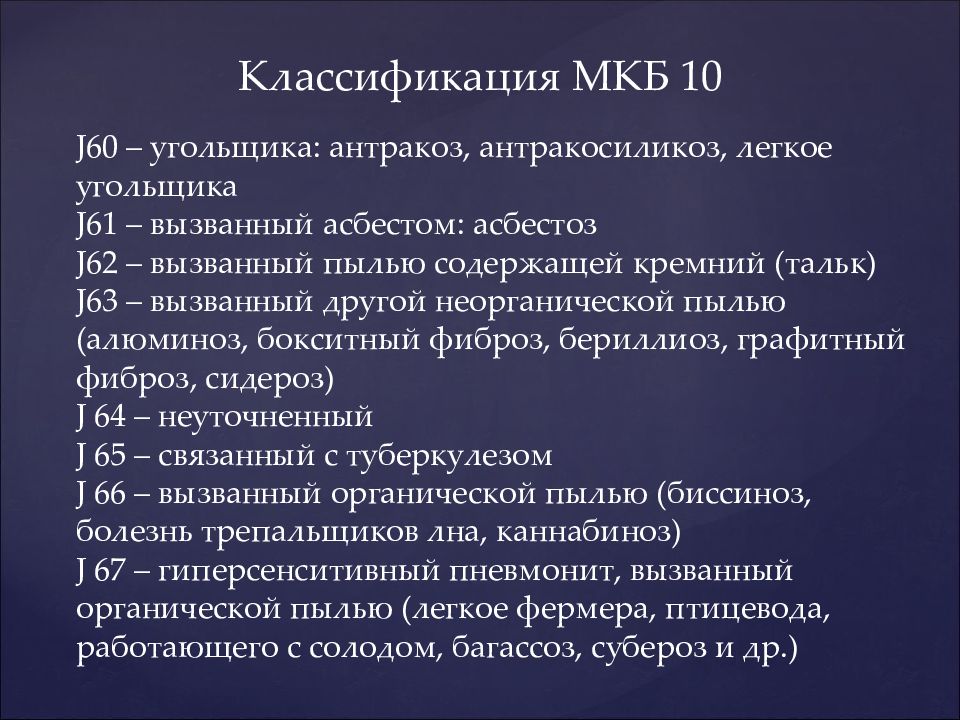

Код мкб 10 атерома головы

Код мкб 10 атерома головы 109 фото